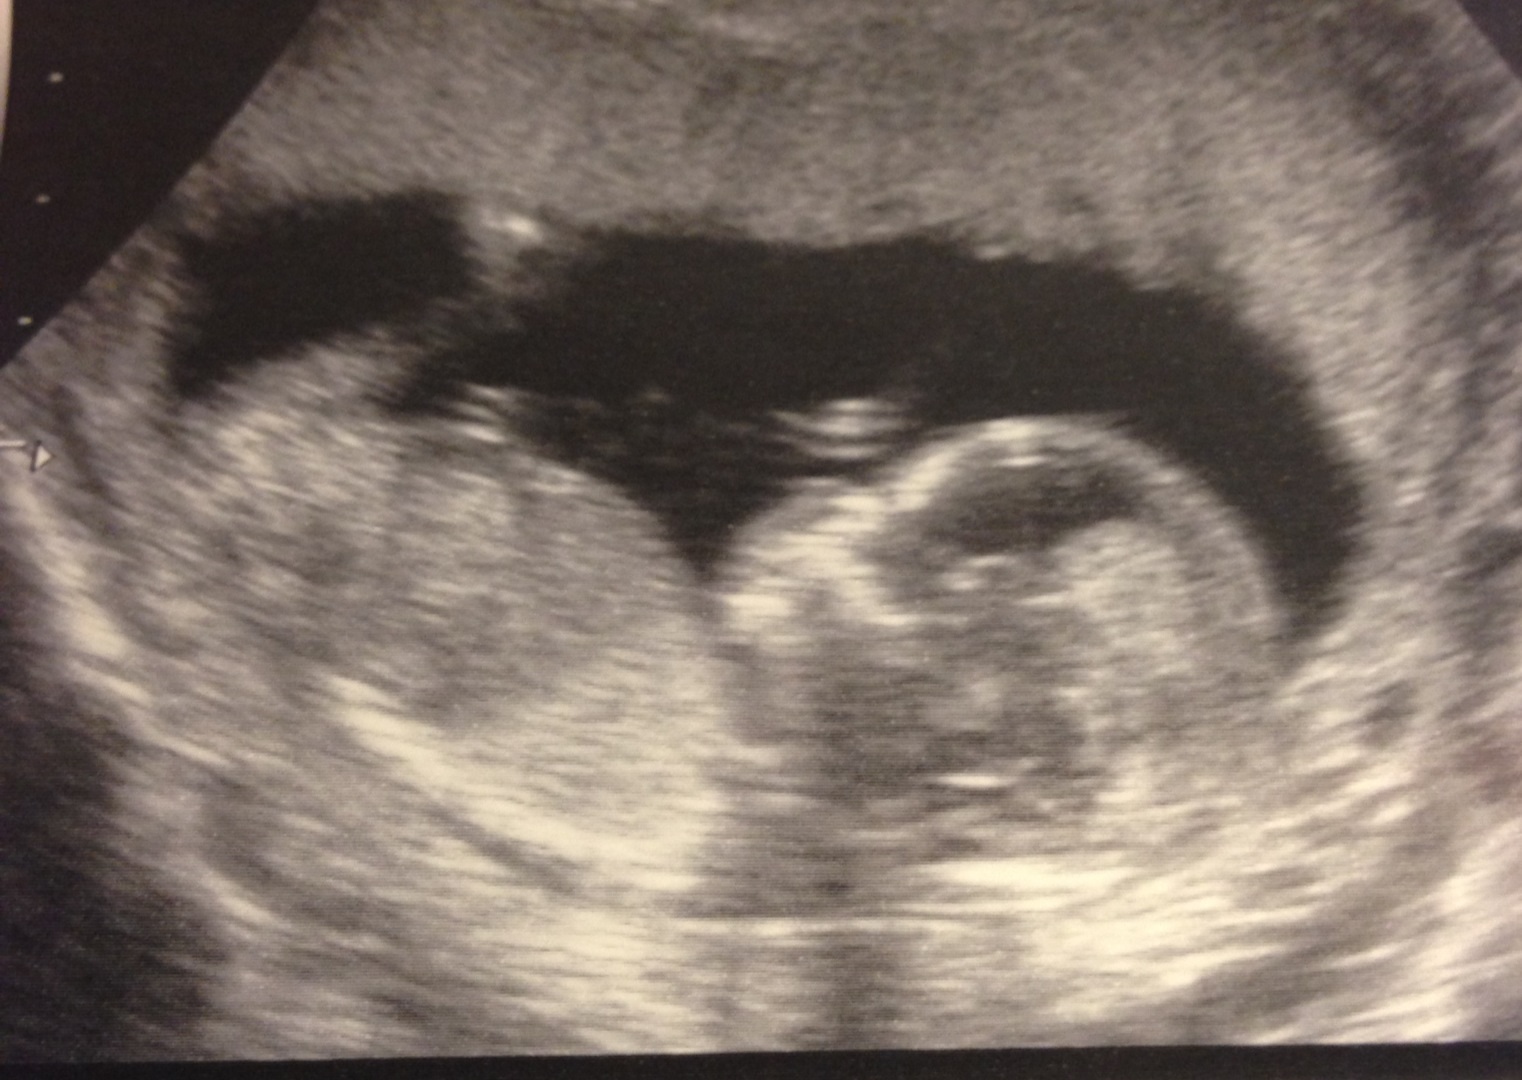

The tech said based on the nub theory, it could go either way. She saw it angled both ways. Not sure if you can see anything in this picture, but thought I'd post for guesses for fun.

We actually are 99% sure we know the sex. :-)